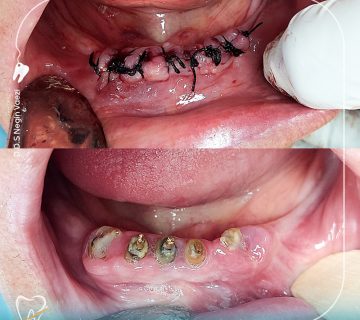

عکس قبل و بعد جراحی و خارج سازی ریشه ها

در تصاویر زیر نیز می توانید وضعیت قبلی دندان ها را قبل و بعد از جراحی مشاهده کنید همینطور دندان های خارج شده را در عکس بعدی می توانید ملاحضه نمایید.